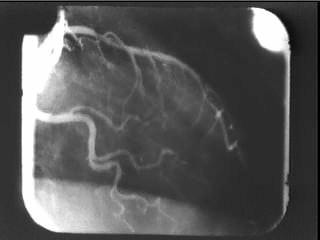

Heart X-ray Image Enhancement

Top: two corresponding angiographic images determined from period trace. Bottom: composite of 5 such corresponding images. Note additional structure visible in composite but not apparent in single raw images.